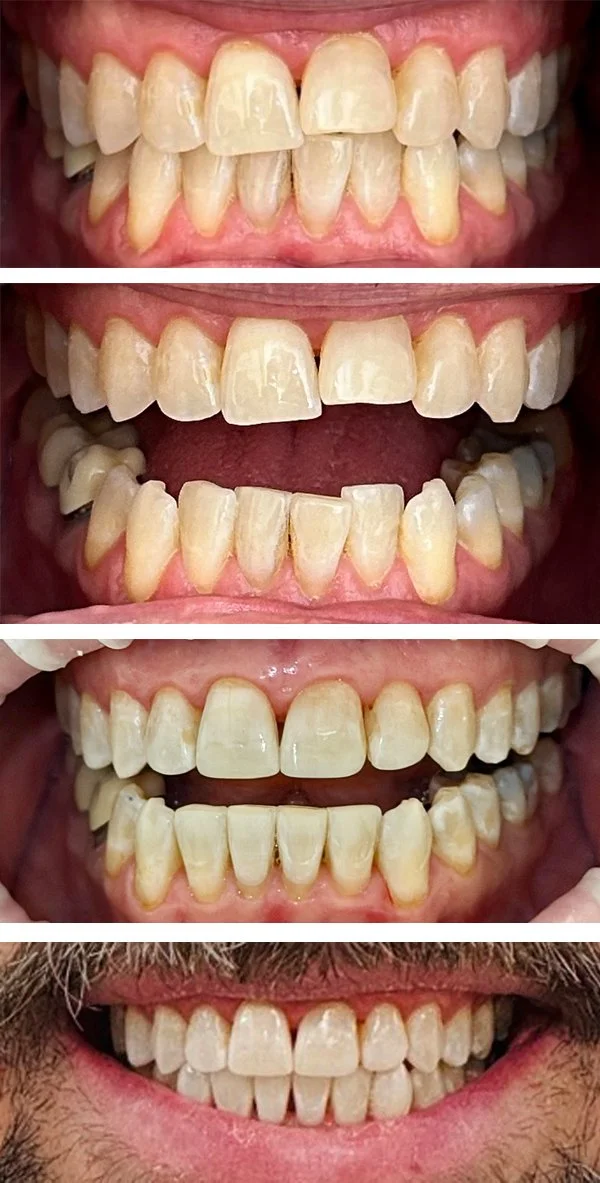

Cosmetics

We can improve the appearance of your teeth in a way tailored to you. Crowns, veneers, tooth shaping, and dental bonding may be used.

Bioclear Restorations, bonding

Restoration

Crown and Bridge